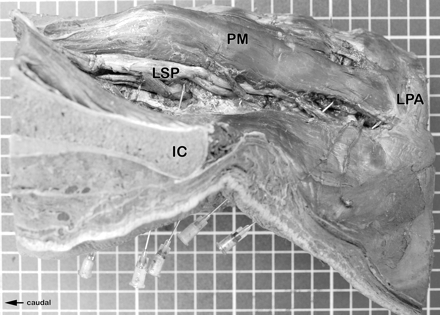

Anatomic dissection of the left side of the injected specimen. The position of the needles can be seen.

Transversal section of the right side of the injected specimen at the level of the third lumbar intervertebral foramen (superior aspect). The deposit of the injected dye can be seen around the third lumbar spinal nerve. The dye also extends to the intramuscular parts of the lumbar plexus (within the psoas muscle).

Transversal section of the right side of the injected specimen at the level of the second lumbar intervertebral foramen (superior aspect). The deposit of the injected dye can be seen around the second lumbar spinal nerve.